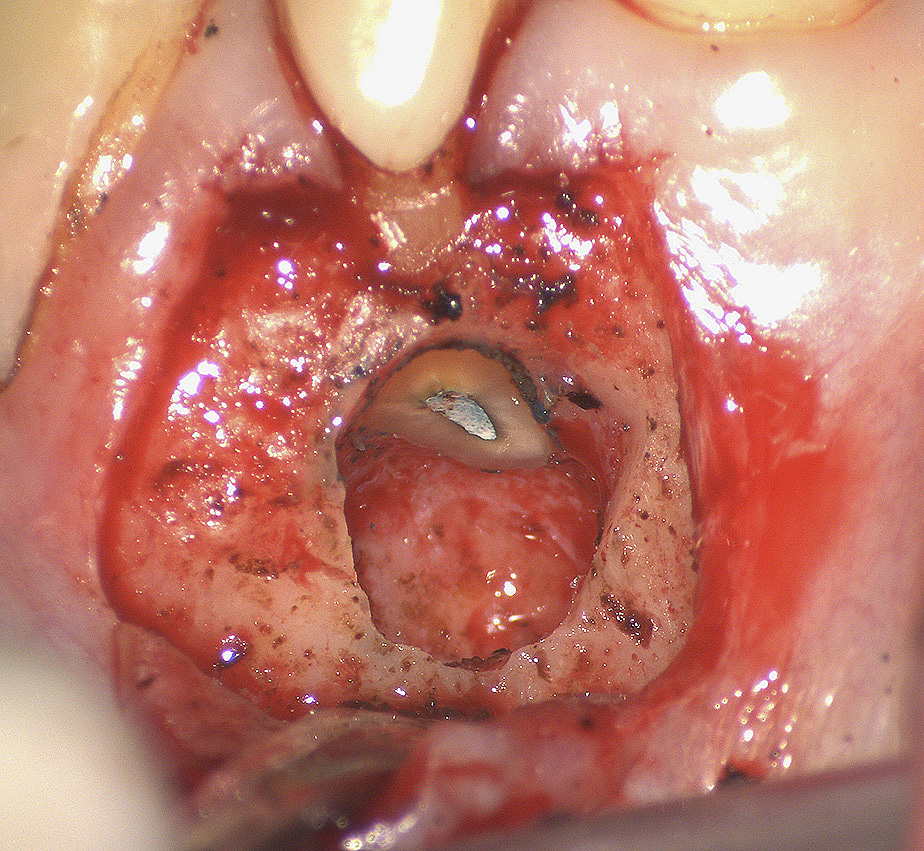

In chirurgia endodontica (apicectomie) il microscopio operatorio permette di individuare, osservare e curare ciò che ad occhio nudo o con ingrandimenti minori sarebbe impossibile vedere, mettendo in evidenza ogni piccolo particolare in modo chiaro ed evidente e di conseguenza alzando notevolmente il livello di cure e quindi di probabilità di successo al termine delle nostre terapie.